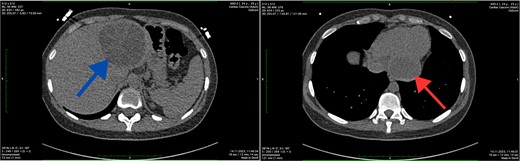

The abdominal ultrasound revealed evidence of cyst formation in the left lobe of the liver, measuring ~10.0 × 8.0 cm in size. Additionally, a bend in the gallbladder neck was observed, accompanied by moderate bile stasis. On the transesophageal echocardiogram, no blood clots were detected in the left atrial appendage or cardiac cavities. The CT scan revealed uniform filling of the left portions of the heart with a contrast agent, indicating an absence of filling defects. Notably, structures within the myocardium near the diaphragm on the posterior lower wall of the left ventricle were identified as round-oval formations with clear contours. These formations exhibited densities ranging from +12 Hounsfield units to +44 Hounsfield units and measured 5.4 × 4.2 × 2.7 cm. Moreover, imaging of the left lobe of the liver depicted a heterogeneous structure attributed to the presence of a cystic formation. This formation displayed a density of up to +17 Hounsfield units and manifested as a round-oval structure with thickened walls. The cyst contained septa and areas of calcification, measuring up to 7.8 × 7.5 cm. Based on the CT scan findings, a diagnosis of echinococcal cyst was established. The presence of echinococcal cysts was noted in both the myocardium of the left ventricle of the heart and in the liver (Fig. 1).

Axial CT scan showing the cystic lesion in the left lobe of the liver (blue arrow) and axial CT scan showing the cystic lesion in the left ventricle (red arrow).